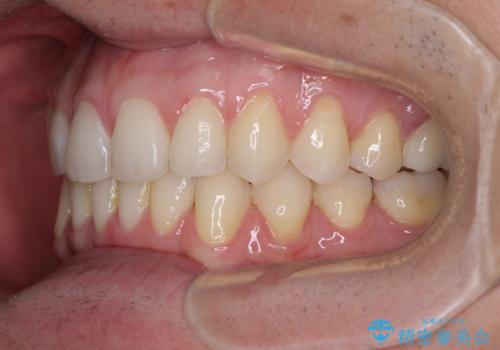

ディープバイトと叢生 インビザラインによる矯正治療

- 前歯のディープバイトと叢生を気にして来院された患者様です。

目立ちにくい装置を希望されていたため、ワイヤー装置とインビザラインを提案したところ、インビザラインを希望されました。

上下ともに叢生が認められたため、親知らずすべてを抜歯し、歯列全体を後方へ移動させることで歯列を整えることとしました。

上顎奥歯の銀歯も気になっていたので、矯正治療の途中でセラミッククラウンへ変更し、その後歯列を仕上げていくこととしました。

ディープバイトもデコボコも改善され、気になっていた銀歯もセラミックとなり、患者様には大変満足していただきました。